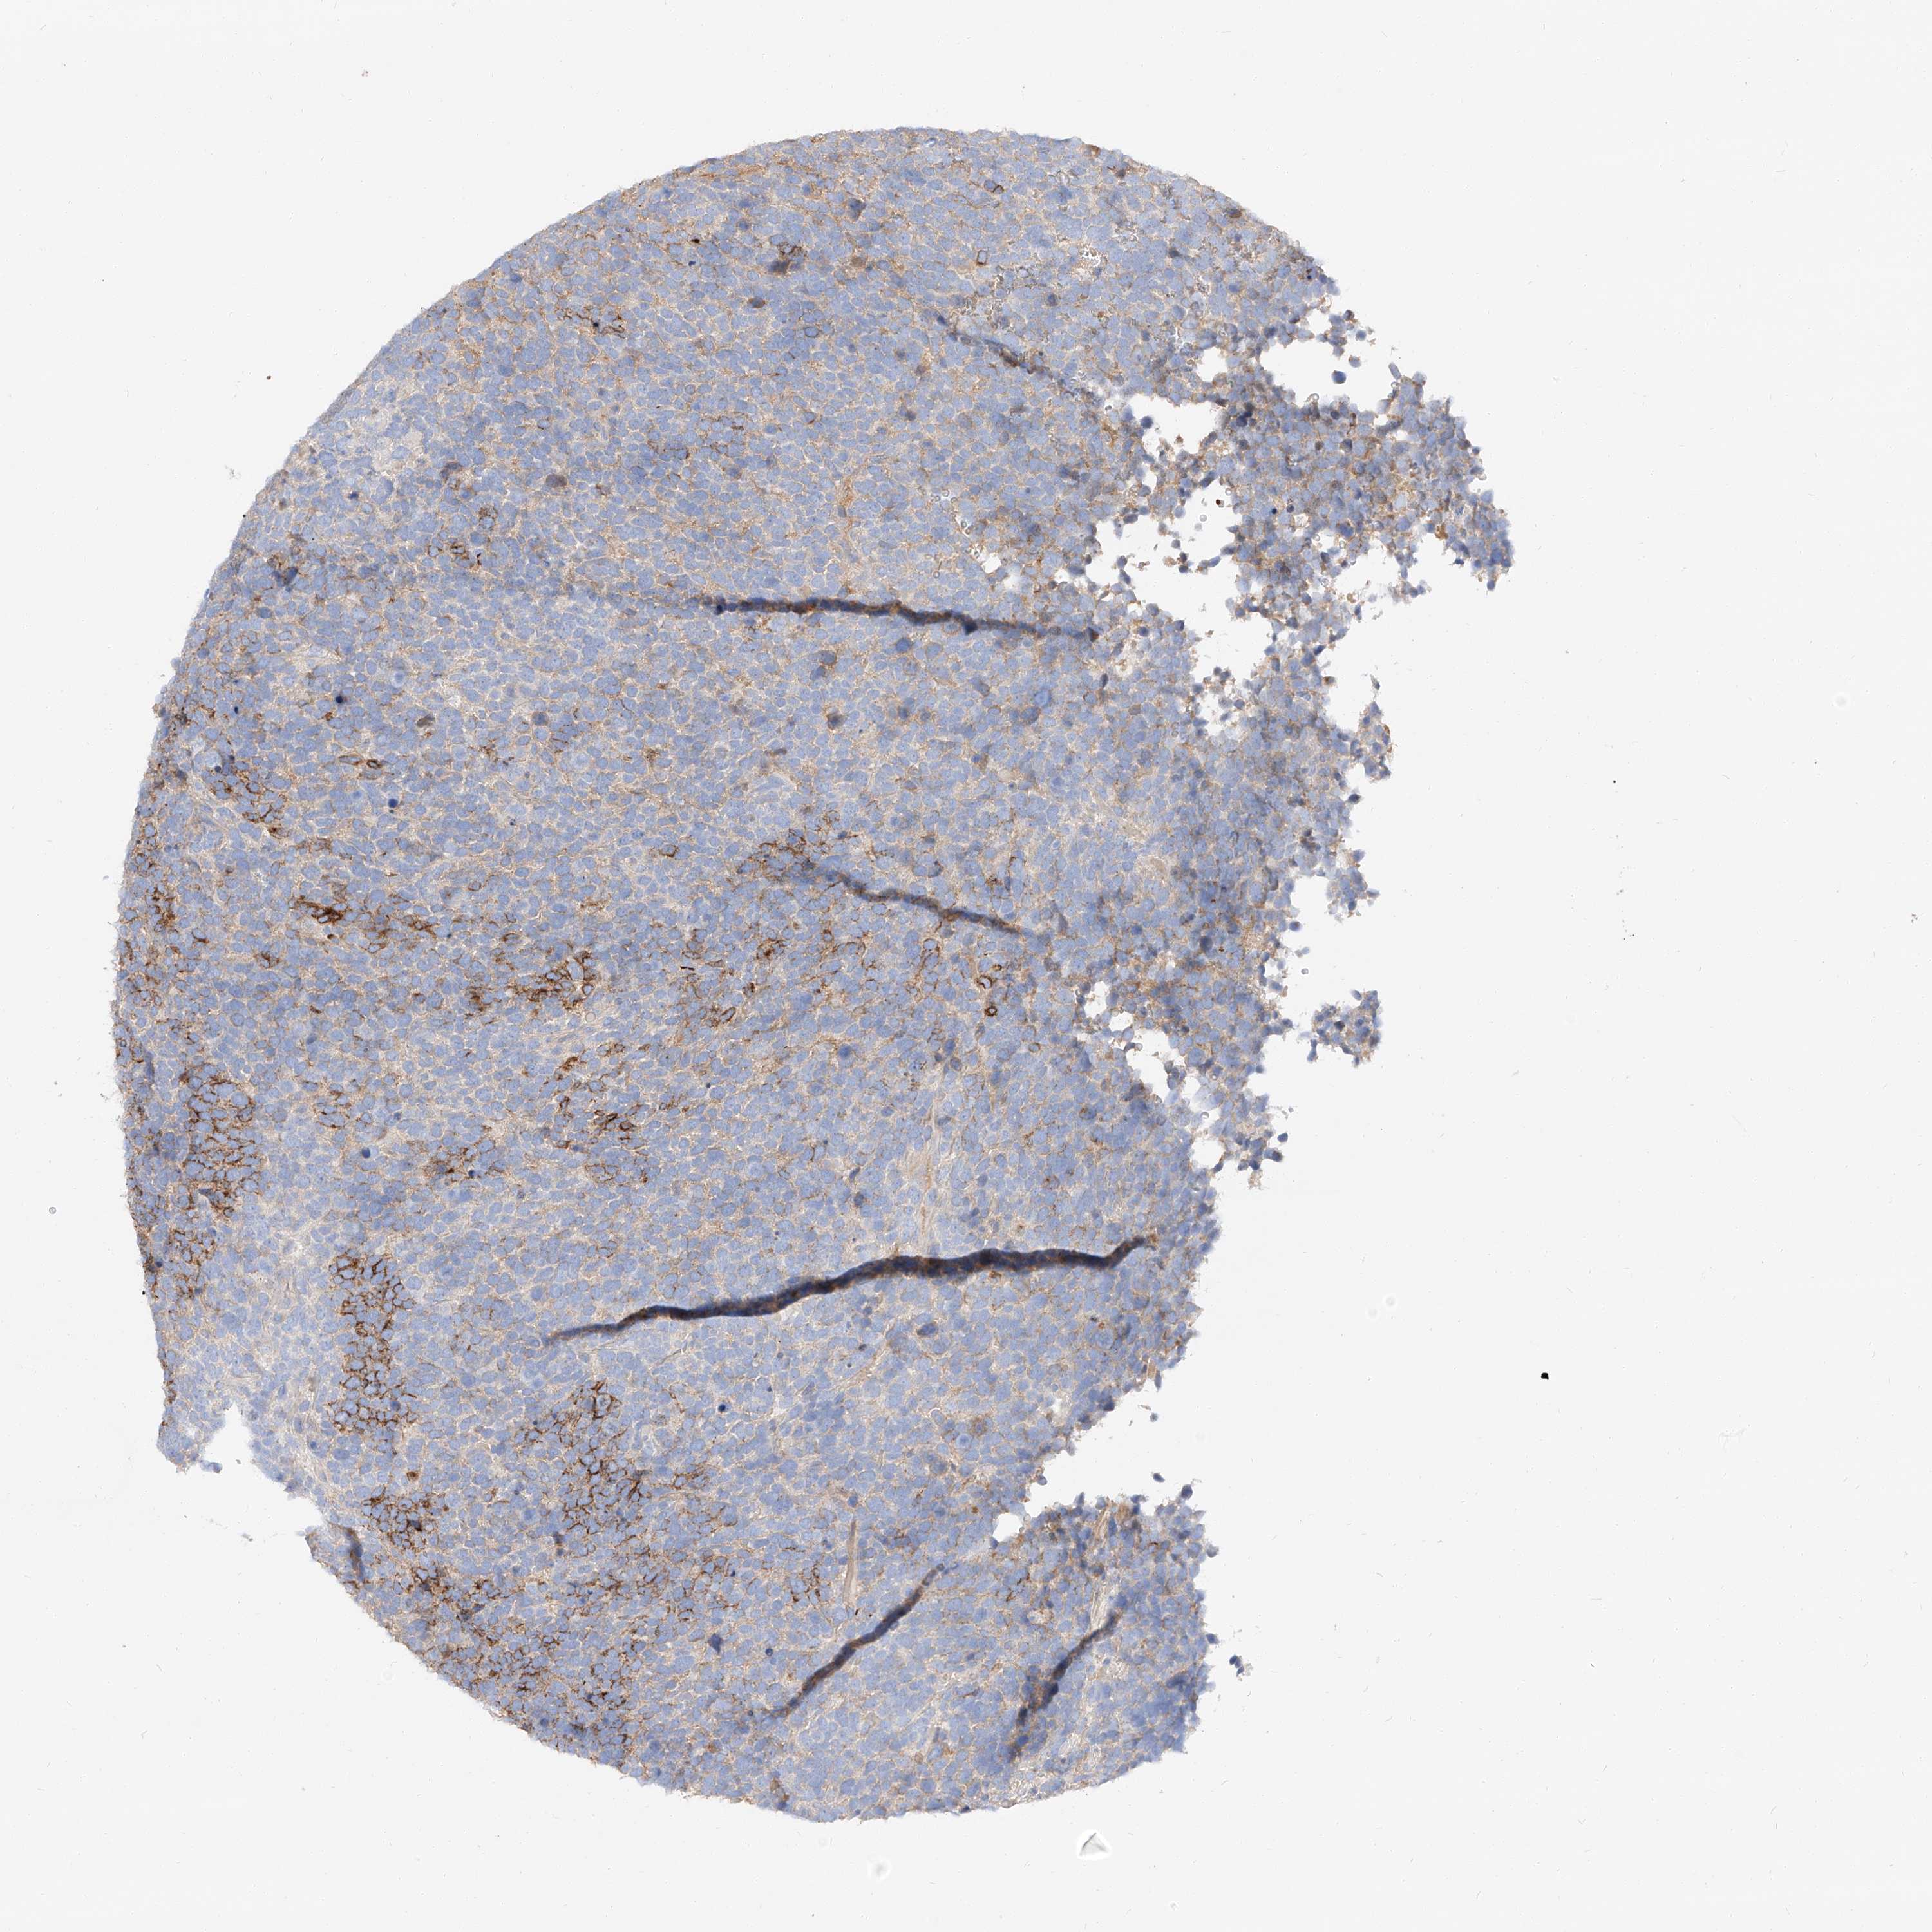

UROTHELIAL CANCER - Protein expressioni

A mouse-over function shows sample information and annotation data. Click on an image to view it in a full screen mode. Samples can be filtered based on level of antibody staining by selecting one or several of the following categories: high, medium, low and not detected. The assay and annotation is described here.

Note that samples used for immunohistochemistry by the Human Protein Atlas do not correspond to samples in the TCGA dataset.

Antibody stainingi

Antibody staining in the annotated cell types in the current human tissue is reported as not detected, low, medium, or high, based on conventional immunohistochemistry profiling in selected tissues. This score is based on the combination of the staining intensity and fraction of stained cells.

Each image is clickable and will lead to virtual microscopy that enables deeper exploration of all samples and also displays staining intensity scores, fraction scores and subcellular localization as well as patient and tissue information for each sample.

Antibody HPA029712

Antibody HPA029713

Staining

High

Medium

Low

Not detected

Intensity

Strong

Moderate

Weak

Negative

Quantity

>75%

75%-25%

<25%

None

Location

Nuclear

Cytoplasmic/membranous

Cytoplasmic/membranous,nuclear

Urothelial carcinoma, Low grade

Urothelial carcinoma, High grade